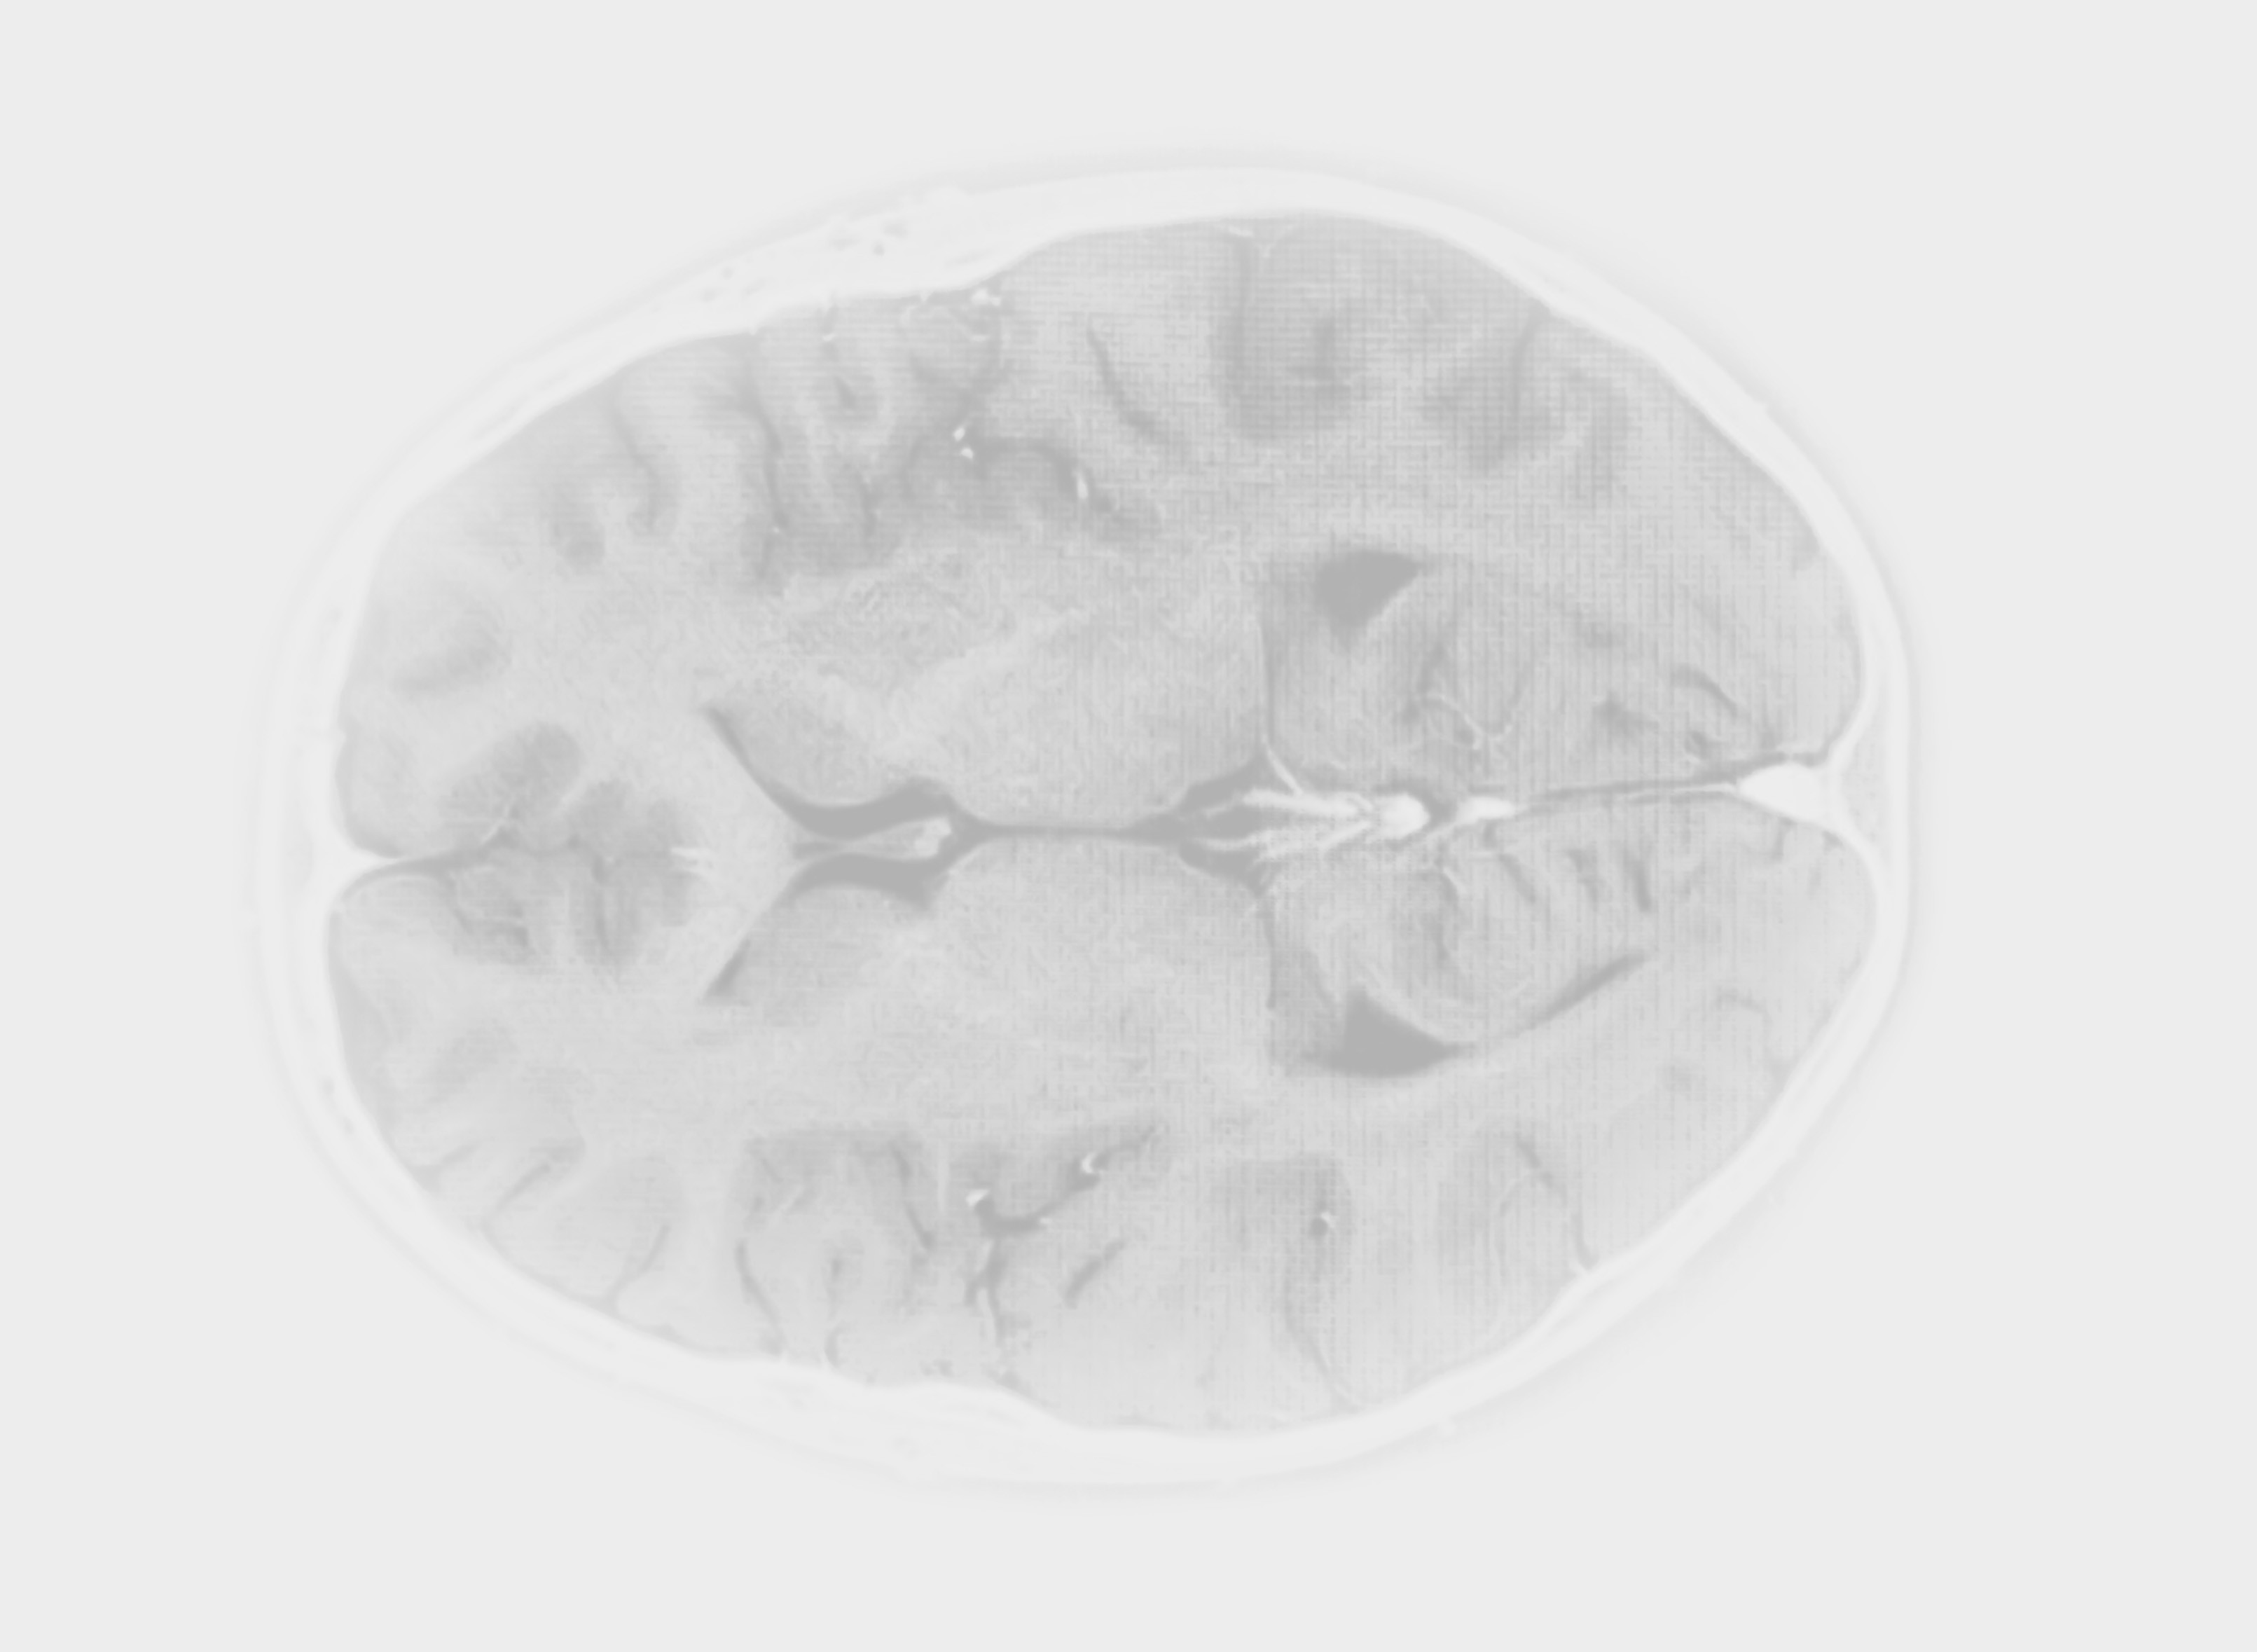

How it looks in practice

See how Carebot works in practice. Compare the image with AI and without AI.

Without Carebot

With Carebot